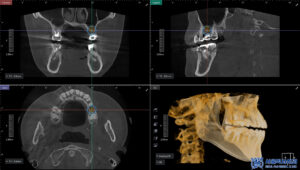

임플란트 식립 전에는 CT 촬영을 통해

뼈의 두께와 높이,

신경과의 거리 등을

정밀하게 확인했습니다.

CT 결과를 바탕으로 식립 각도와

깊이를 세밀하게 계획하고,

충분한 뼈 지지가 확보될 수 있도록

맞춤형 임플란트 계획을 수립하였습니다.